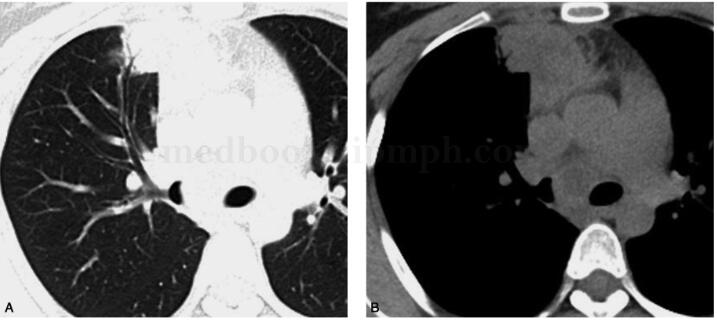

2010年5月6日我院增强CT检查:右肺上叶前段病变伴多发纵隔淋巴结增大,原发性TB可能性大,恶性不除外(图1)。

图1 纵隔内多发软组织密度团块伴液化坏死,增强扫描实质部分明显强化;右肺上叶前段斑片实变灶,内见支气管充气征,增强扫描其内亦见液化坏死区